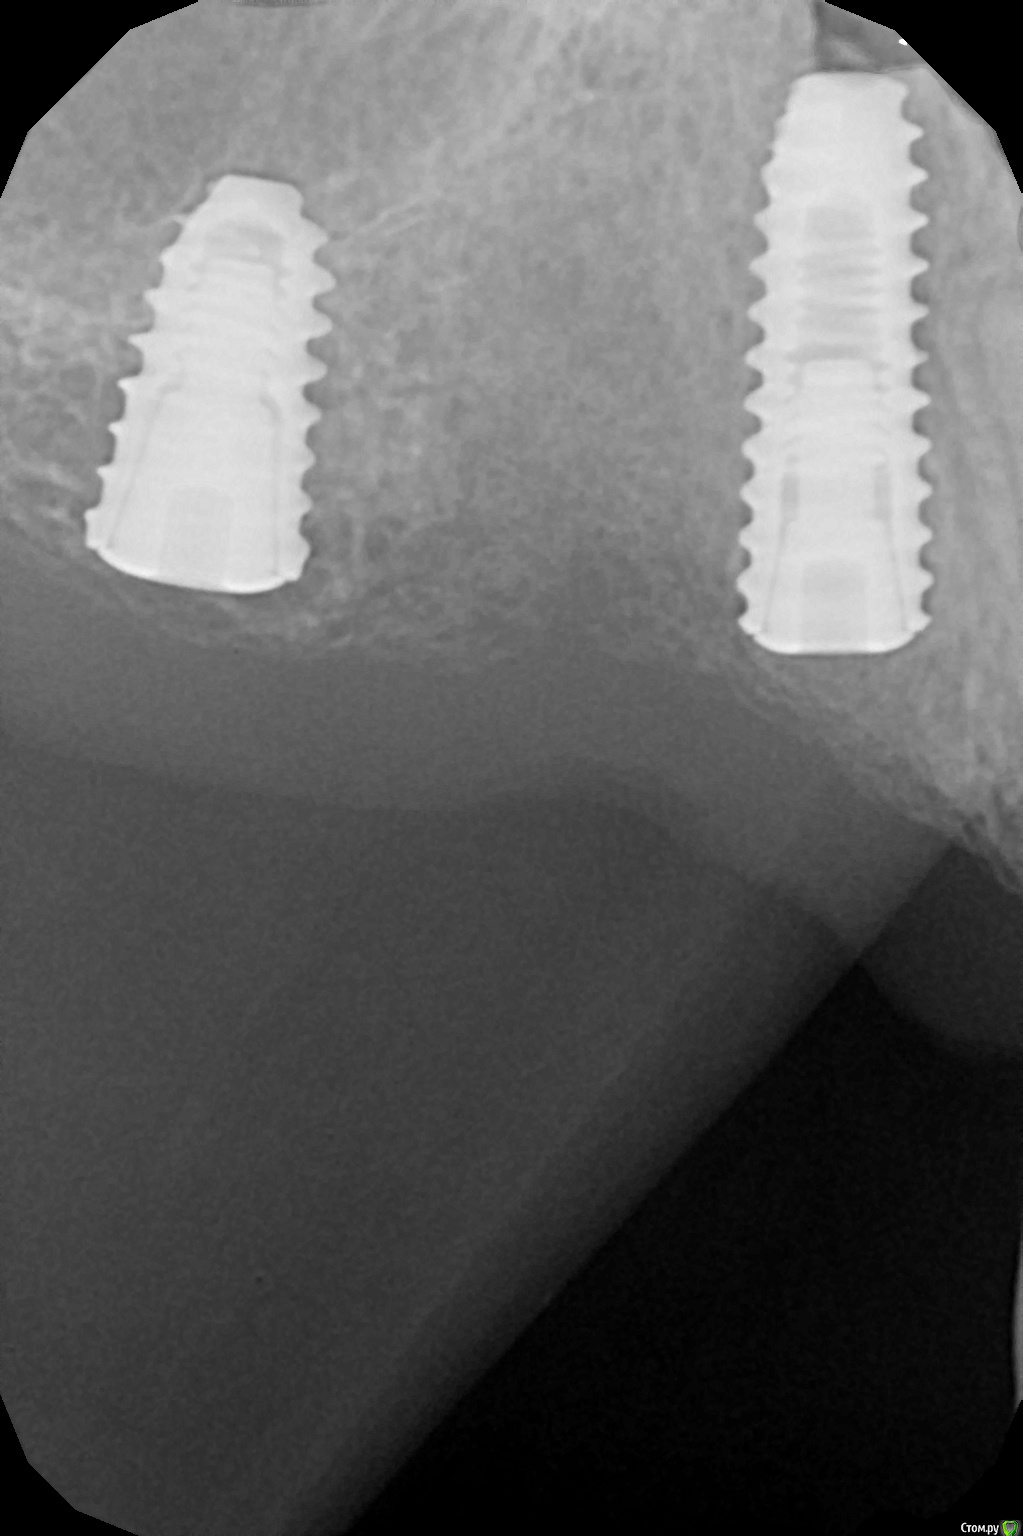

kamranchick Опубликовано 19 декабря, 2018 Поделиться Опубликовано 19 декабря, 2018 проведено удаление зубов. 14-15-16 с одномоментной имплантацией. торк около 10 ньютон. раны велись открыто. 5 Ссылка на комментарий

Nazim_NV86 Опубликовано 20 декабря, 2018 Поделиться Опубликовано 20 декабря, 2018 второй 4х7 ? Ссылка на комментарий

kamranchick Опубликовано 21 декабря, 2018 Автор Поделиться Опубликовано 21 декабря, 2018 второй 4х7 ?ага. тс4 Ссылка на комментарий

kamranchick Опубликовано 21 декабря, 2018 Автор Поделиться Опубликовано 21 декабря, 2018 Вестибулярно кость сохранена?да конечно Ссылка на комментарий